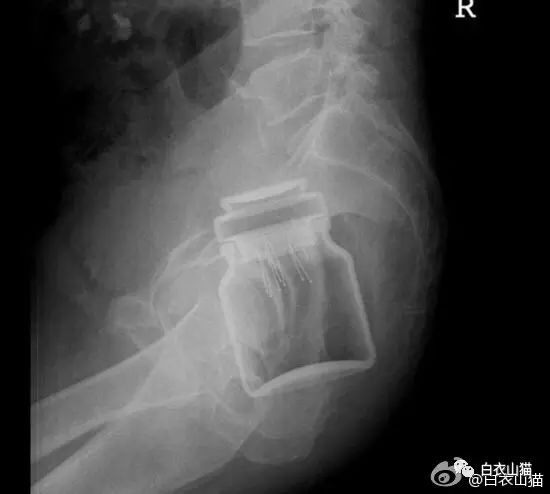

这个还是比较常见的,认得出来吗?

男性病人,也是个杯子。

这个也是一个玻璃杯。